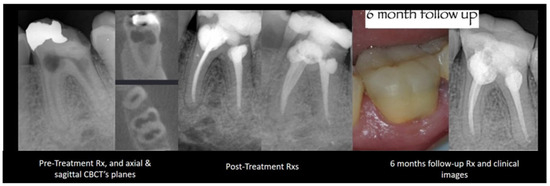

2.4. Resorptions